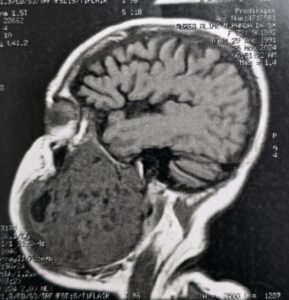

O tumor, diagnosticado como um ameloblastoma agressivo, comprometia aproximadamente 50% da mandíbula esquerda da paciente, provocando deformidade facial severa, além de grandes dificuldades para se alimentar e se comunicar. Natural do estado do Pará, a paciente convivia com o problema há oito anos e chegou a perder 30 quilos nos últimos meses.

A cirurgia mobilizou médicos altamente especializados das áreas de bucomaxilofacial, microcirurgia de cabeça e pescoço, além de cirurgia plástica. De acordo com o cirurgião bucomaxilofacial Flávio Fayad, o planejamento do procedimento envolveu exames detalhados e discussões clínicas ao longo dos últimos meses. “Foi uma cirurgia complexa, mas conduzida com precisão. Realizamos a ressecção completa do tumor, instalamos uma placa de reconstrução mandibular e, por fim, fizemos um enxerto de fíbula vascularizada, técnica que utiliza parte do osso da perna para reconstruir a mandíbula”, explicou.